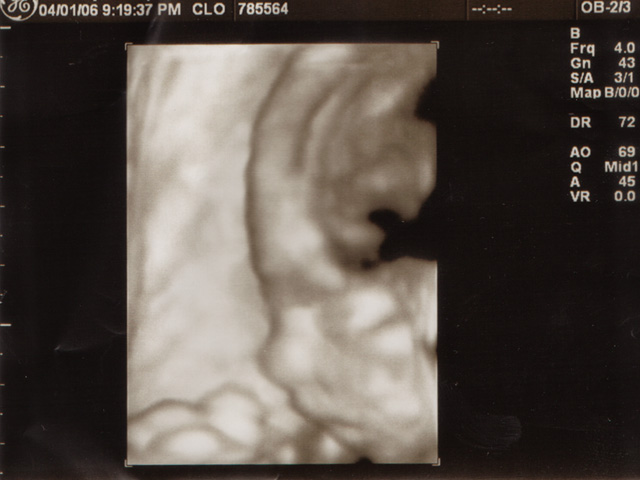

My sonograms.

<Click on the photo for a larger view>